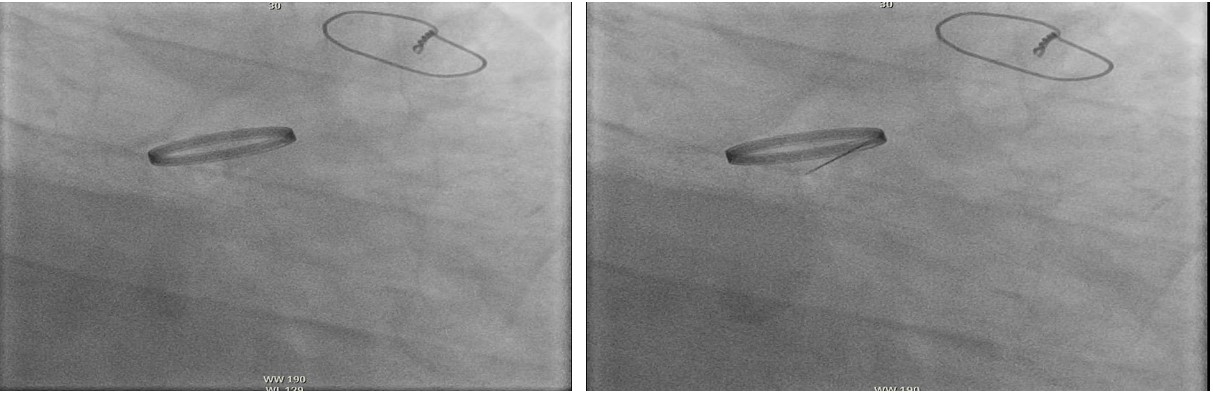

Transthoracic echocardiography (TTE) revealed a peak gradient of 3.7 m/s and mean gradient of 28 mmHg across the prosthetic valve. Urgent transesophageal echocardiography (TEE) showed severely restricted leaflet motion with torrential aortic regurgitation—highly suggestive of valve thrombosis. Due to prohibitive surgical risk, thrombolysis with alteplase (25 mg over 6 hours) was administered. Repeat TEE demonstrated improved leaflet motion (velocity 2.2 m/s, mean gradient 17.6 mmHg), LVEF of 25%, and new severe mitral regurgitation. He was stabilized on milrinone and extubated by hospital day five.